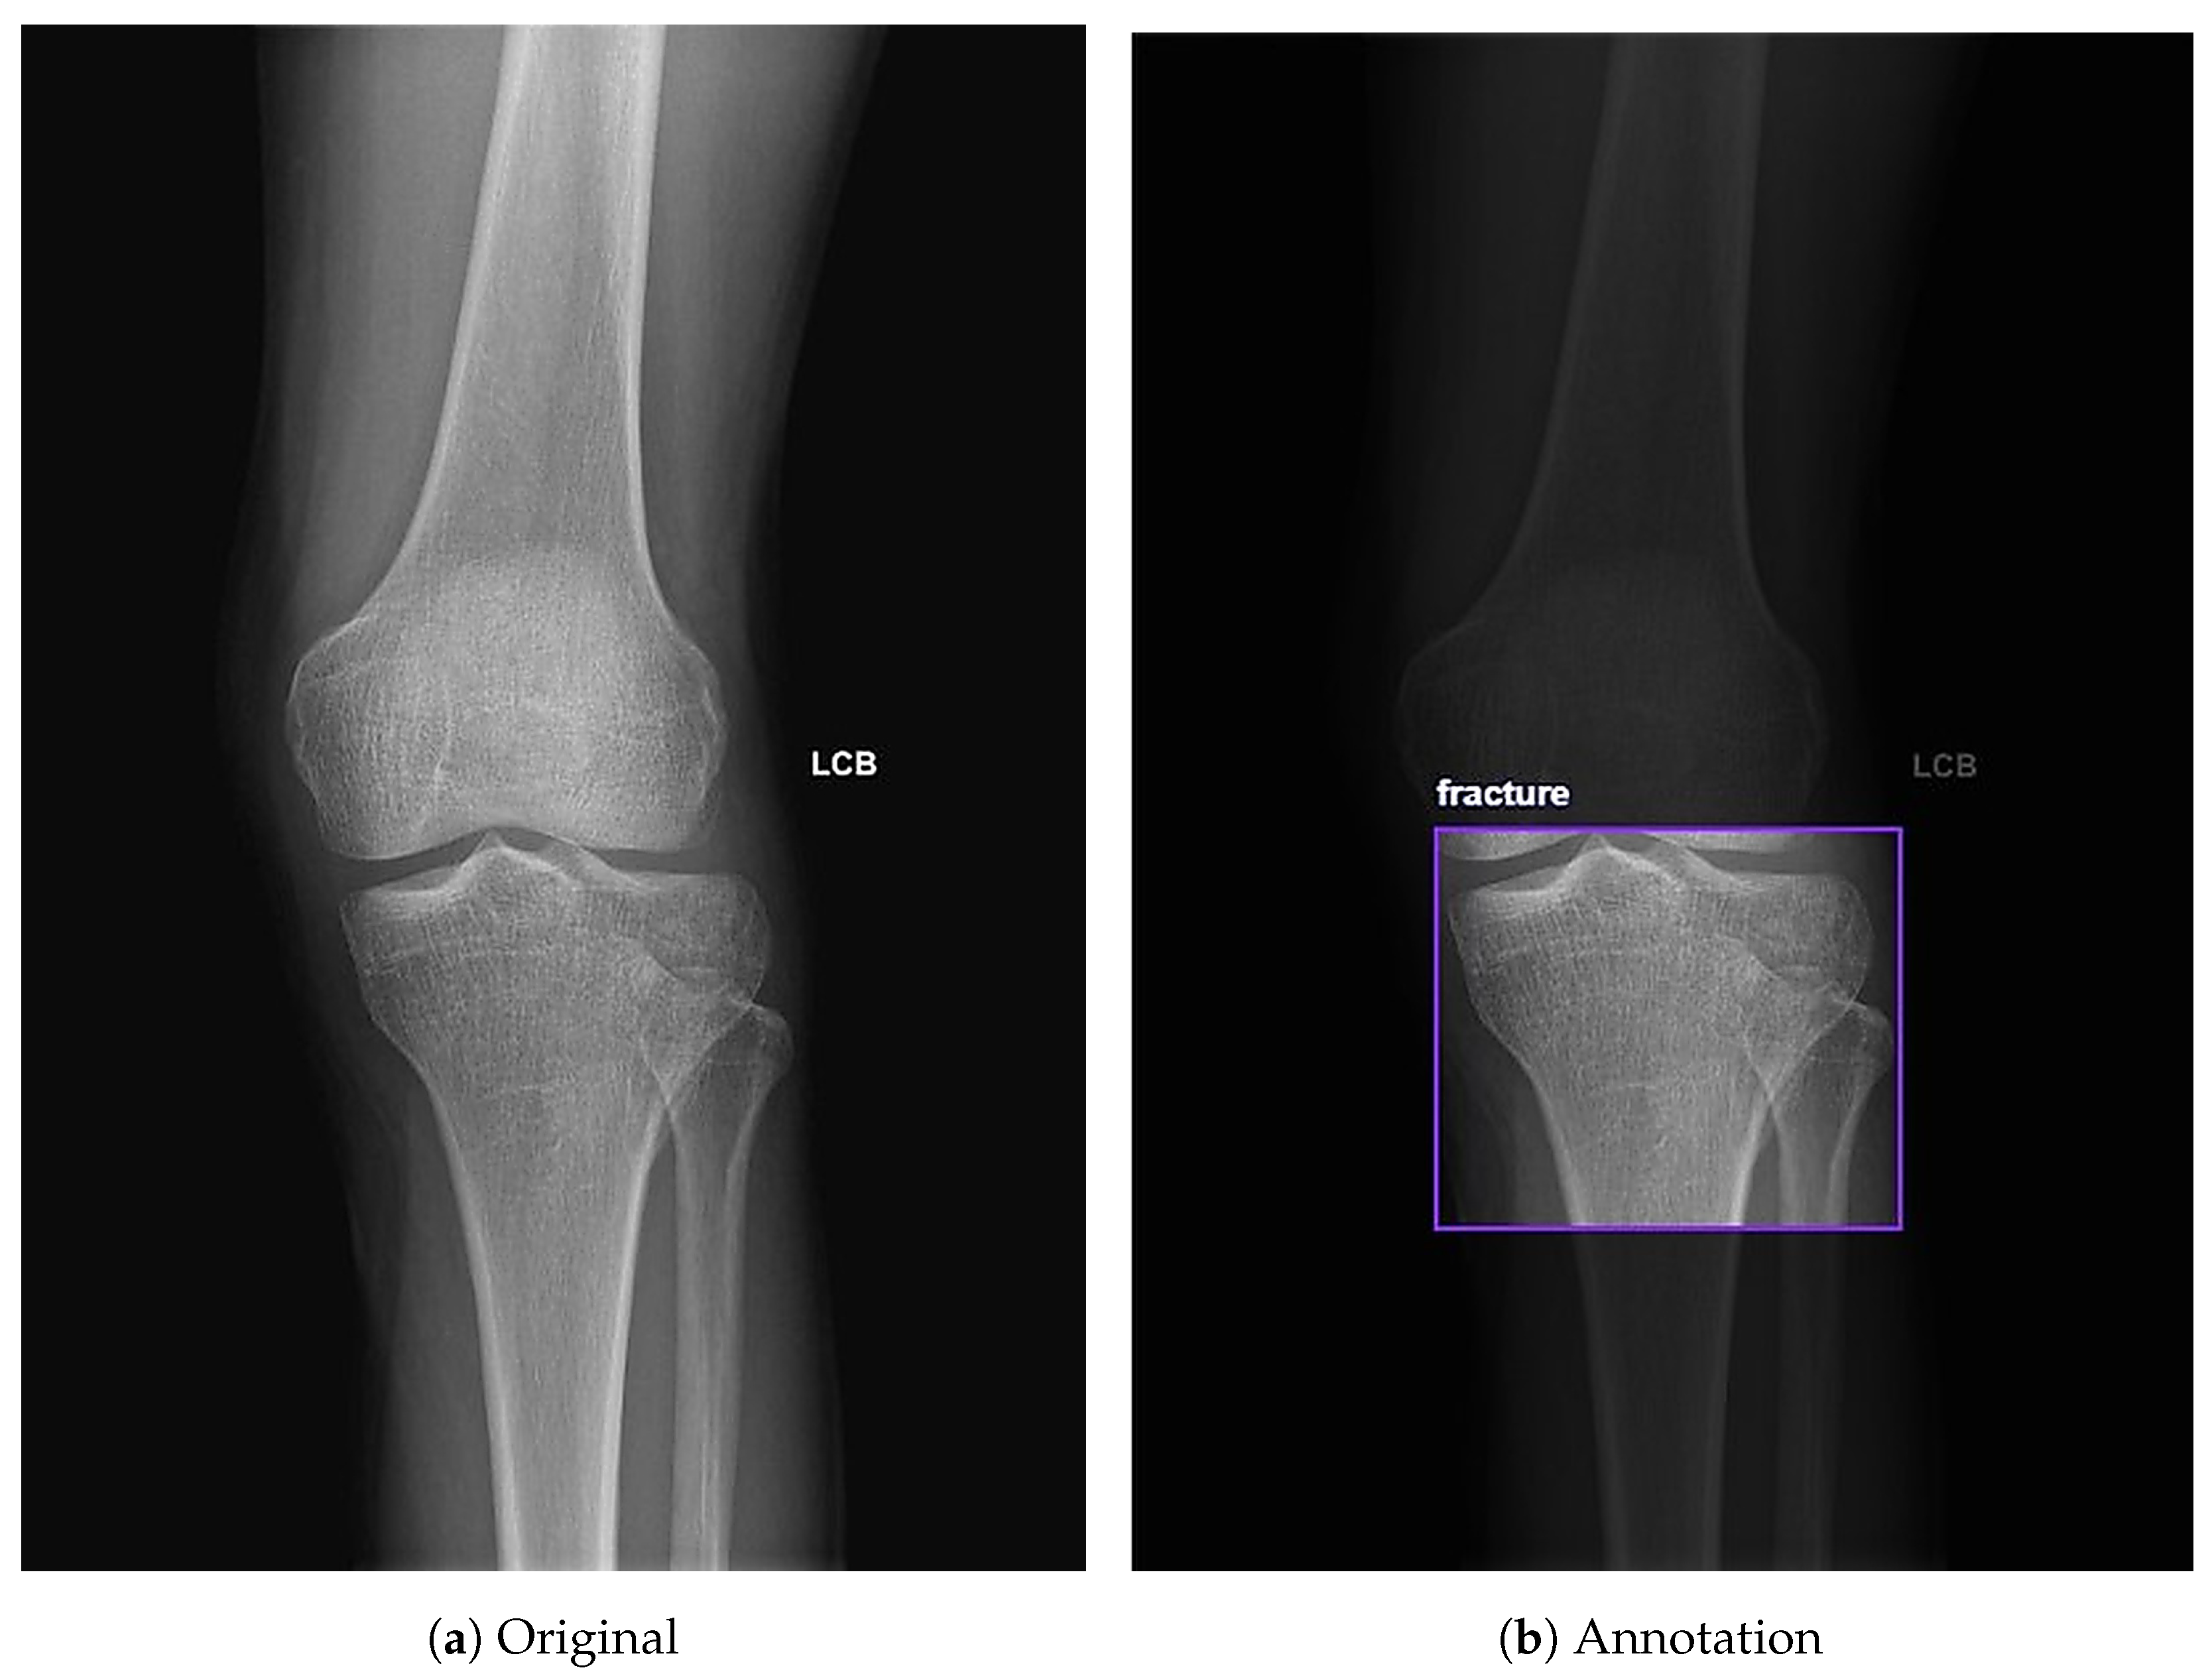

3.3. Data Annotation